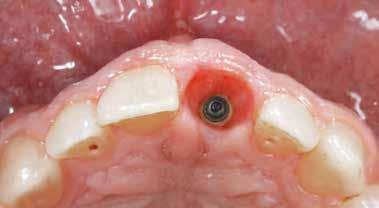

Helyi érzéstelenítést (4% articain, 1:100.000 adrenalin) követően a pácienseket arra kértük, hogy 5 percig 0,2%-os klórhexidin oldattal öblögessenek. Minimálinvazív lebenyt képeztünk 15c pengével és elemeltük az alveoláris csont bukkális felszínéről. Miután az alveoláris gerincet feltártuk, felhelyeztük a sebészeti sablont. Ezután az implantátum helyét maximum 350 fordulat/ perc fordulatszámú fúróval előkészítettük, és steril fiziológiás sóoldattal átmostuk. Az implantátum helyének előkészítése után eltávolítottuk a sebészeti sablont és behelyeztük az implantátumot az implantátum stabilitási görbéjének és csúcsának helyes mérése érdekében. Az implantátum behelyezése során rögzítettük a behelyezési nyomatékgörbét (insertion torque curve, ITC) és e görbe csúcsát, amelyet behelyezési nyomatékértéknek (insertion torque value, ITV) is nevezünk. Az implantátum behelyezéséhez, valamint az ITC és ITV rögzítéséhez W&H készüléket (SA-310 W&H Elcomed implantációs egységek, W&H, Burmoos, Ausztria) használtunk. Egy steril, SmartPeg nevű felépítményt csatlakoztattunk az implantátumhoz, és az implantátum stabilitását az Osstell® Mentor készülékkel (W&H, Burmoos, Ausztria) ellenőriztük. Végül gyógyulási csavart helyeztünk be, és 6,0-ás varratokat használtunk a lebeny rögzítéséhez. Posztoperatívan, a behelyezett implan-

tátum kiértékelésére periapikális röntgenfelvételt készítettünk Rinn röntgentartó készülék és párhuzamos long cone technika segítségével (2a-e. ábra).

2. ábra: A klinikai vizsgálatban részt vevő 36 beteg egyikének esete, aki két különböző felületű implantátumot kapott. A 26-os pozícióban lévő implantátum MultiNeO CS (kontrollcsoport), míg a 27-es pozícióban lévő implantátum MultiNeO NH CS volt (tesztcsoport). (a): 15c szikével crestálisan bemetszést végeztünk. (b): Az implantátumágy előkészítéséhez 3D nyomtatott implantációs sebészi sablont használtunk a gyártói protokoll szerint. (c): Az implantátum beültetése után megmértük az implantátum stabilitási hányadost. (d): A mucoperiosteális lebenyeket a felépítményekhez igazítottuk és a sebet varratokkal zártuk. (e): Periapikális röntgenfelvételt készítettünk az implantátumok behelyezése után (kiindulási állapot). (f): 15 nap múlva a varratokat eltávolítottuk a posztoperatív klinikai vizsgálatot követően. (g): Az ISQ-érték miatt a végleges restaurációt T45 időpontban helyeztük be. (h) T45 időpontban periapikális röntgenfelvételt készítettünk. (i) A virtuális implantátumtervezés fotója.